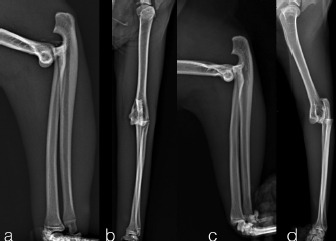

Two, spayed, Domestic Shorthaired cats with an age of 1.5 years (case 1) and 6 years (case 2) were referred to the author’s clinic for the non-weight bearing left forelimb lameness after a suspected trauma. Physical examination, of both cats, revealed moderately swollen and painful left elbow, with abnormal posture characterized by extended rotation of antebrachium and supination of the paw. Orthogonal radiographs of forelimbs demonstrated a complete caudal elbow luxation (Fig. 1). The radius and ulna were caudally and proximally displaced in relation to the humerus; furthermore, in case 1, a small avulsion bone fragment (2 mm diameter) closed to the lateral aspect of the humeral condyle was presented. No other abnormality was identified during the physical and radiographic examinations. The cats were sedated by intramuscular administration of dexmedetomidine (Dexdomitor: Pfizer Italia Srl, Rome, Italy) (10 μg/kg) and methadone (Semfortan: Dechra Veterinary Products Srl, Turin Italy) (0.4 mg/kg). General anesthesia was induced with propofol (Proposure: Merial Italia Spa, Milan, Italy) (6 mg/kg) intravenously and, after oro-tracheal intubation, maintained with isoflurane (IsoFlo: Aesica Queenborough Limited, Kent, United Kingdom) and oxygen. Modified closed reduction technique was attempted in both cases. Distal traction of antebrachium with full extension of the elbow was initially achieved followed by simultaneously applying distal pressure on the olecranon and partial elbow flexion. Following successful reduction, the collateral ligaments integrity was indirectly assessed with the Campbell’s test (1971), with normal limits value around 110° of supination and 70° of pronation recorded in both patients. The joint stability and reduction were maintained with gentle manipulation. However, instability was present at 100° of elbow extension, while major stability was obtained at 40° of flexion. For this reason, the elbow was held at 40° of flexion and a simple transarticular external skeletal fixator type IIa was applied to maintain the stability of the joint. Due to the forced flexion position, which limited the biomechanics movement, the cats were not able to weight bearing in the postoperative period. Two full pins, smooth Kirschner wires 2.0 mm of diameterf were inserted in the proximal third of the diaphysis of the humerus and in the distal third of the radial diaphysis. Stainless steel connecting bars (Gènia. St. Hilaire de Chaléons, France) (3.0 mm) were positioned medially and laterally connecting with Maynard clamps (Gènia. St. Hilaire de Chaléons, France) to the full pins (Fig. 2). The avulsion bone fragment was not treated in case 1. The patients were discharged from the clinic 24 hours after surgery. Cage rest without any exercise was recommended for 2 weeks and meloxicam (Meloxoral: Fatro S.p.A., Ozzano Emilia, Italy) (0.05 mg/kg) was administrated for 7 days.

Fig. 1. Pre-operatively radiographs in lateral (a, c) and cranio-caudal (b, d) view. Case 1 (a–b); case 2 (c–d).